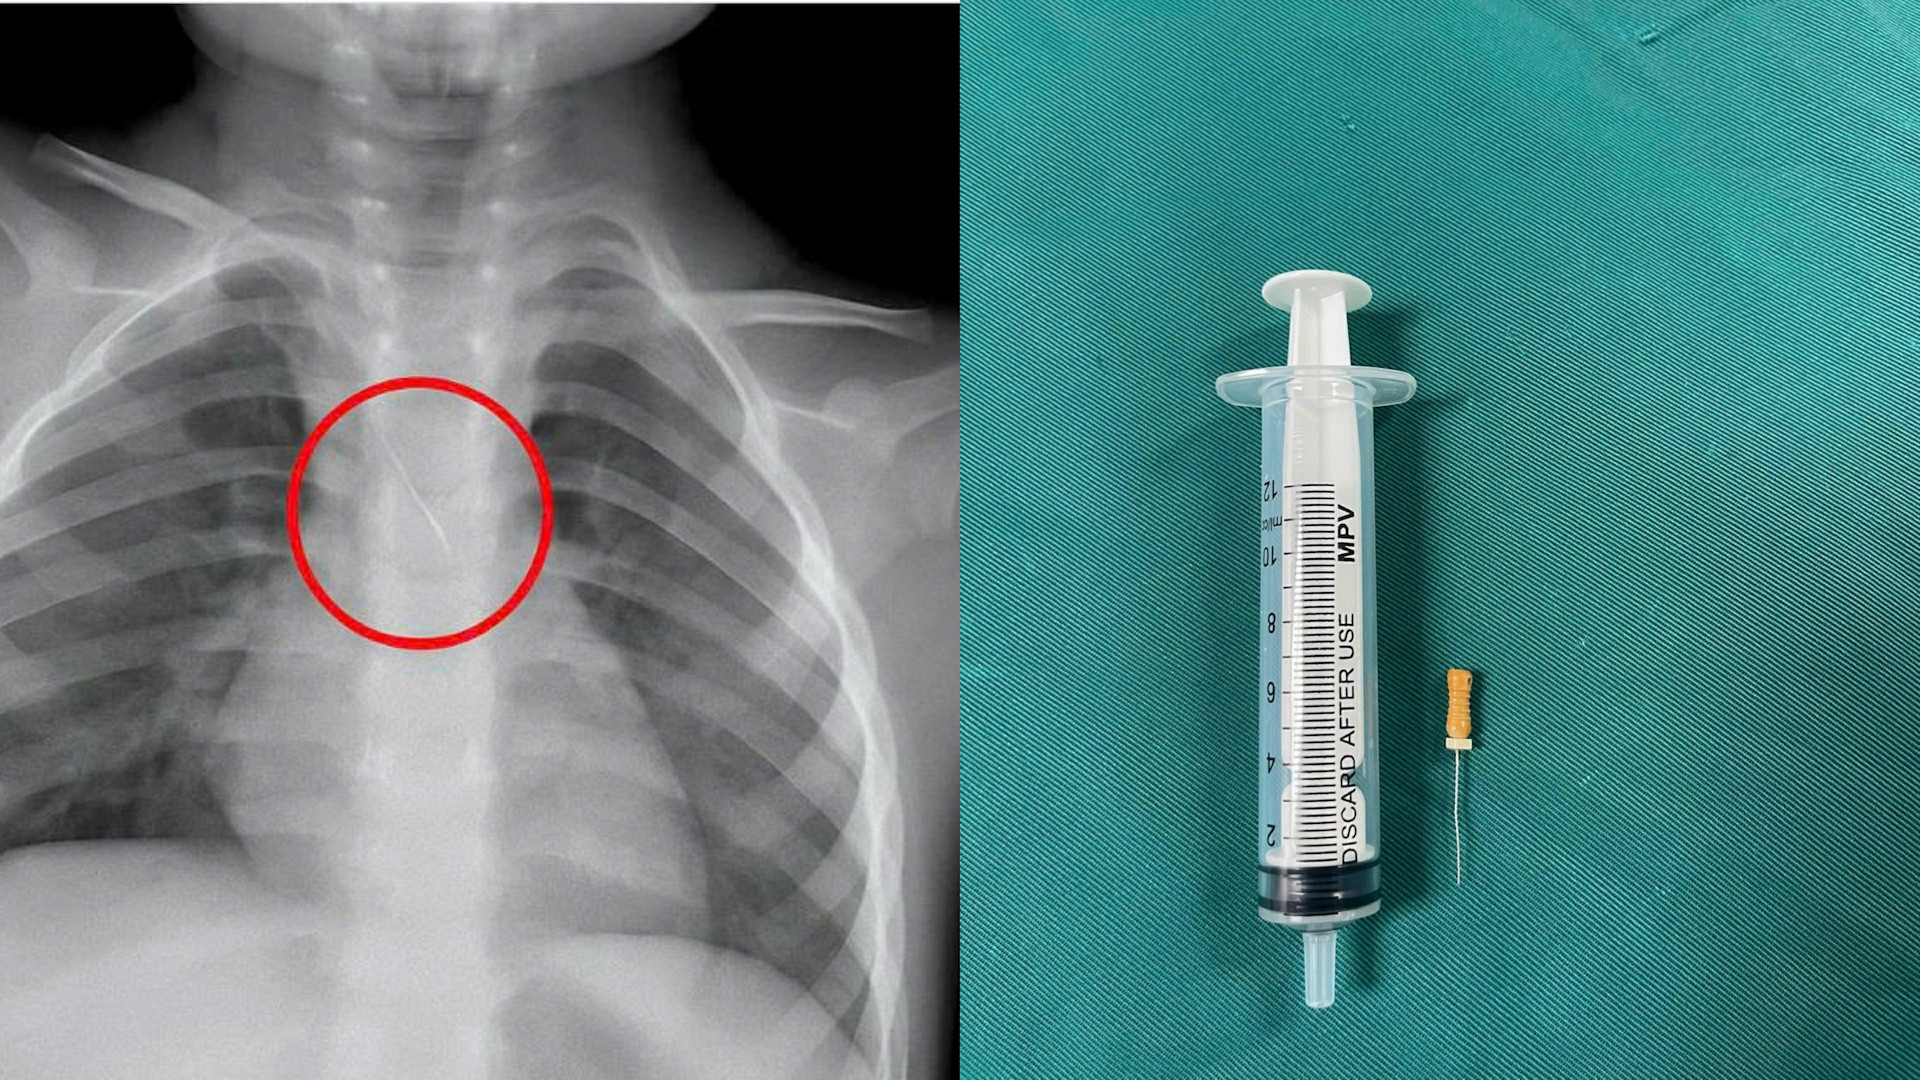

Trước đó, bệnh nhi N.Q.T.Đ. (3 tuổi, trú tại xã Cửa Việt) nhập viện trong tình trạng ho nhiều, ho sặc. Kết quả chẩn đoán hình ảnh cho thấy, bệnh nhi bị sặc kim chọc tủy vào đường thở.

Dị vật này dài khoảng 22mm, nằm ở góc carina (nơi vùng chia đôi khí quản), một đầu nhọn cắm vào 1/3 dưới khí quản, một đầu tròn nằm trong phế quản gốc trái.

Các bác sĩ đánh giá, đây là trường hợp cấp cứu vô cùng nguy hiểm. Các y, bác sĩ của bệnh viện đã hội chẩn liên khoa và tiến hành nội soi phế quản cấp cứu. Sau khoảng 15 phút, các bác sĩ đã gắp thành công dị vật ra ngoài. Các triệu chứng trước đó của bệnh nhi đã được cải thiện.